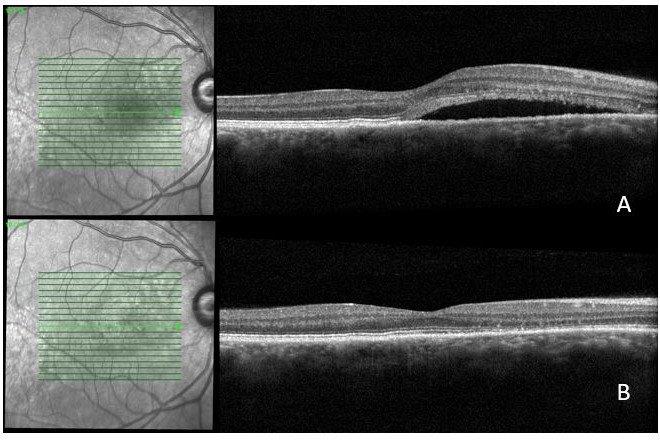

A 65-year-old man who’d noticed vision disturbance in his right eye for the past three months. Previously he had left CSCR which resolved after a prolonged period of observation. His acuity was 6/7.5 right and 6/6 left. Reviewing his previous imaging, there was choroidal thickening which gradually resulted in an enlarging pigment epithelium detachment (PED) in an area of the right macula with mild drusen. The large PED subsequently developed a microbreak with mild deflation, and surrounding fibrin and subretinal fluid when he became symptomatic (Fig 5).

Although there was an improvement in the amount of subretinal fluid three months after his right eye became symptomatic, there was still significant fibrin on the OCT imaging and a fluorescein angiogram showed an ongoing leak. Half-fluence PDT therapy was performed without any complications.